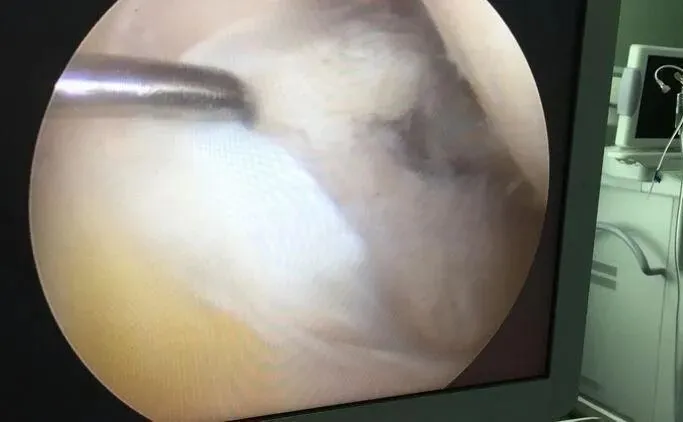

类风湿关节炎是一种自身免疫性疾病,病友们的免疫系统会“认不出”自己的关节组织,反而错误地发起攻击,最先遭殃的就是滑膜。被攻击后的滑膜会发炎、增生、变厚,从原来薄薄的一层,变成充血水肿、摸起来粗糙的“病变组织”——这就是咱们需要清理的“问题滑膜”。

增生变厚的病变滑膜,就像一张粗糙的砂纸,会不停地摩擦、侵蚀关节软骨。而关节软骨一旦受损,是没法再生的,长期下去,关节间隙会变窄、骨头会被破坏,最后可能出现手指“天鹅颈”畸形、关节僵硬得动不了,这种损伤是不可逆的。